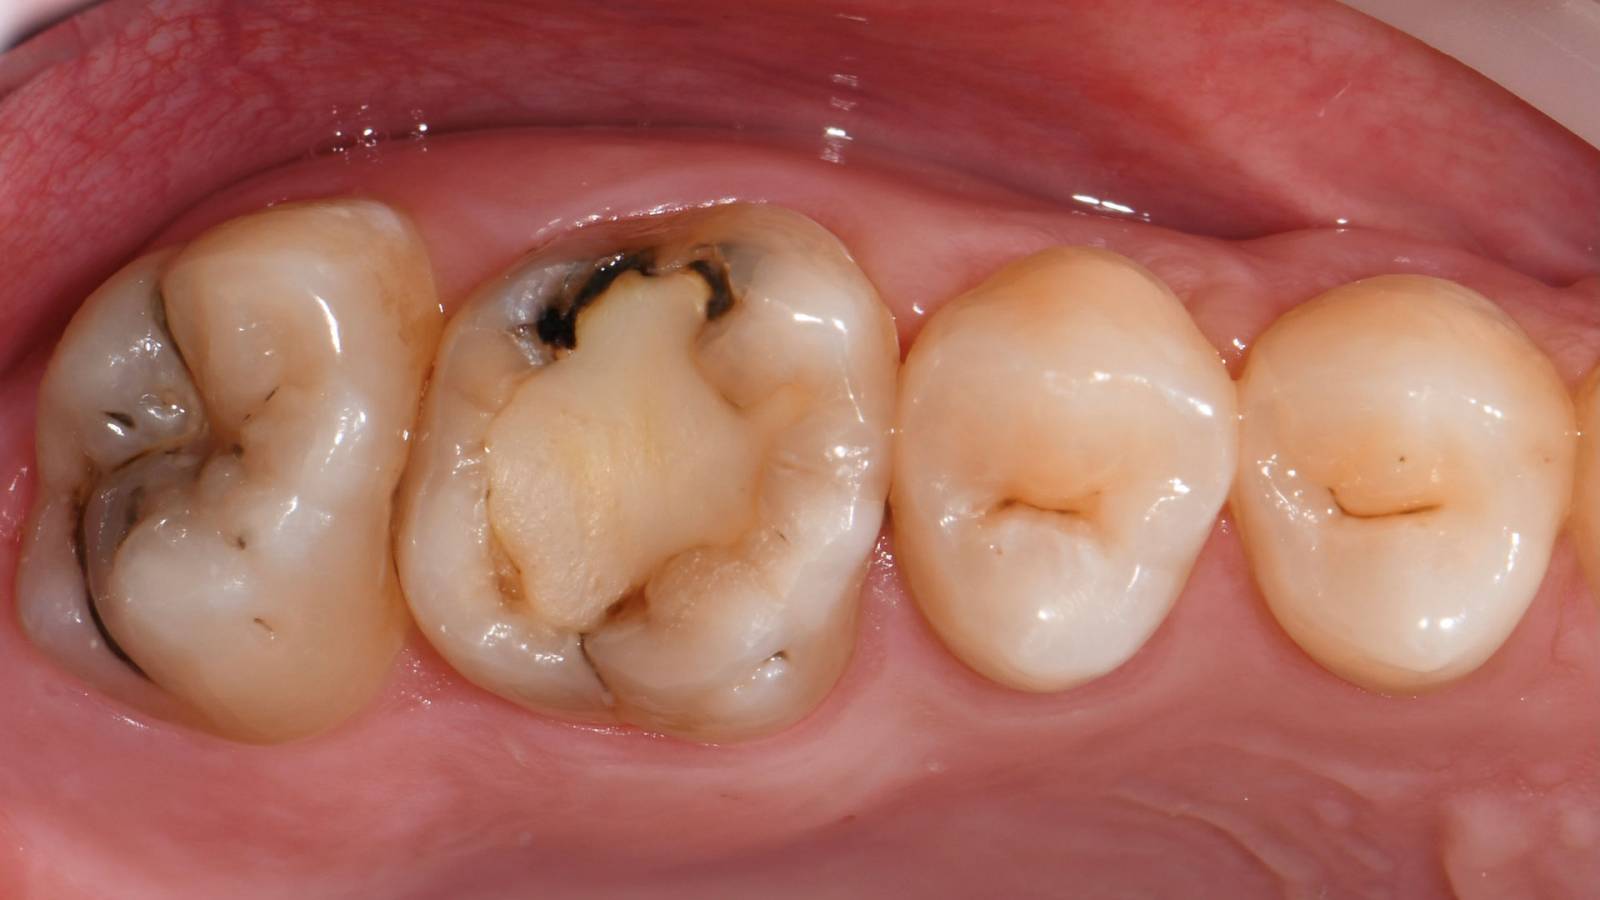

Before: Failed amalgam restoration needing replacement. Patient complaining of sensitivity and tooth presenting multiple cracks.

Before: Pre-operative clinical scenario after endodontic therapy.